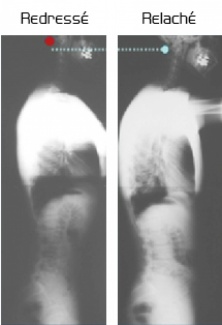

En réponse aux préoccupations esthétiques liées à la silhouette, SPINEO est le premier appareil apportant des solutions basées sur l'étude physiologique des fonctions posturales humaines.

L'entraînement postural en redressement axial est l'exercice d'amélioration de la silhouette par excellence.

La stimulation musculaire vertébrale avec SPINEO assure le redressement postural et lutte contre les tassements de la silhouette liés à l'âge ou à l'atonie.

Lors de ce redressement, la contraction abdominale est physiologique et intégrée dans l'activité posturale. Elle s'oppose aux sempiternels exercices gymniques abdominaux et offre enfin des éléments biomécaniques fiables en réponse aux préoccupations esthétiques relatives à cette région anatomique.

L'ouverture costale engendrée par le redressement thoracique se traduit par un redressement du buste et des seins.

Les bénéfices sur la silhouette sont valorisés par la stimulation proprioceptive et la prise de conscience posturale développés lors du travail avec SPINEO.